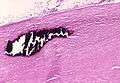

Asbestosis is the scarring of lung tissue (beginning around terminal bronchioles and alveolar ducts and extending into the alveolar walls) resulting from the inhalation of asbestos fibers. There are two types of fibers: amphibole (thin and straight) and serpentine (curly). All forms of asbestos fibers are responsible for human disease as they are able to penetrate deeply into the lungs. When such fibers reach the alveoli (air sacs) in the lung, where oxygen is transferred into the blood, the foreign bodies (asbestos fibers) cause the activation of the lungs' local immune system and provoke an inflammatory reaction dominated by lung macrophages that respond to chemotactic factors activated by the fibers.[11] This inflammatory reaction can be described as chronic rather than acute, with a slow ongoing progression of the immune system attempting to eliminate the foreign fibers. Macrophages phagocytose (ingest) the fibers and stimulate fibroblasts to deposit connective tissue. Due to the asbestos fibers' natural resistance to digestion, some macrophages are killed and others release inflammatory chemical signals, attracting further lung macrophages and fibrolastic cells that synthesize fibrous scar tissue, which eventually becomes diffuse and can progress in heavily exposed individuals. This tissue can be seen microscopically soon after exposure in animal models. Some asbestos fibers become layered by an iron-containing proteinaceous material (ferruginous body) in cases of heavy exposure where about 10% of the fibers become coated. Most inhaled asbestos fibers remain uncoated. About 20% of the inhaled fibers are transported by cytoskeletal components of the alveolar epithelium to the interstitial compartment of the lung where they interact with macrophages and mesenchymal cells. The cytokines, transforming growth factor beta and tumor necrosis factor alpha, appear to play major roles in the development of scarring inasmuch as the process can be blocked in animal models by preventing the expression of the growth factors.[12][13] The result is fibrosis in the interstitial space, thus asbestosis. This fibrotic scarring causes alveolar walls to thicken, which reduces elasticity and gas diffusion, reducing oxygen transfer to the blood as well as the removal of carbon dioxide. This can result in shortness of breath, a common symptom exhibited by individuals with asbestosis.[14]

Asbestosis resembles many other diffuse interstitial lung diseases, including other pneumoconiosis. The differential diagnosis includes idiopathic pulmonary fibrosis (IPF), hypersensitivity pneumonitis, sarcoidosis, and others. The presence of pleural plaquing may provide supportive evidence of causation by asbestos. Although lung biopsy is usually not necessary, the presence of asbestos bodies in association with pulmonary fibrosis establishes the diagnosis.[16] Conversely, interstitial pulmonary fibrosis in the absence of asbestos bodies is most likely not asbestosis.[3] Asbestos bodies in the absence of fibrosis indicate exposure, not disease.